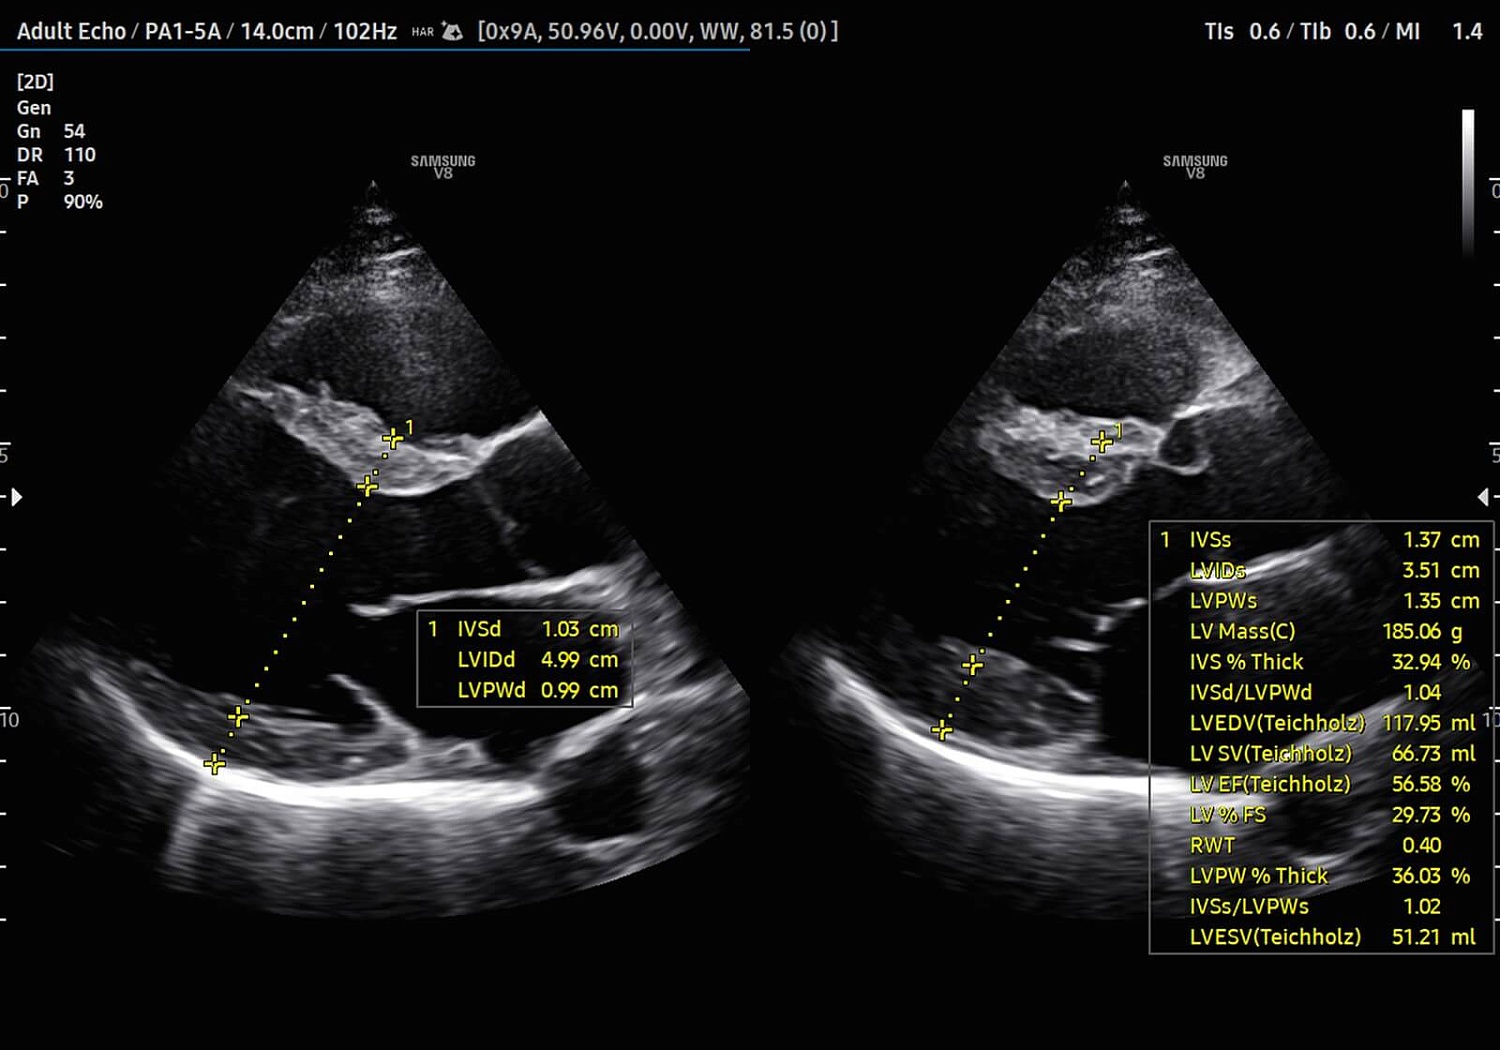

УЗИ аппарат V8 отличается превосходным технологическим оснащением, высочайшим уровнем визуализации и удобством использования. Многочисленные решения позволяют оптимизировать рутинный диагностический процесс, автоматически осуществляя измерения, расчеты и классифицируя выявленные изменения. Это значительно сокращает время на исследование и в разы повышает диагностическую точность. Помимо уже знакомых функций Biometry Assist, AutoIMT, 2D Follicle, 2DNT и пр., в модели реализована опция автоматического сегментирования структур сердца, автоизмерения с технологией Heart Assist, определение положения срединного нерва в поперечном сечении Nerve Track.